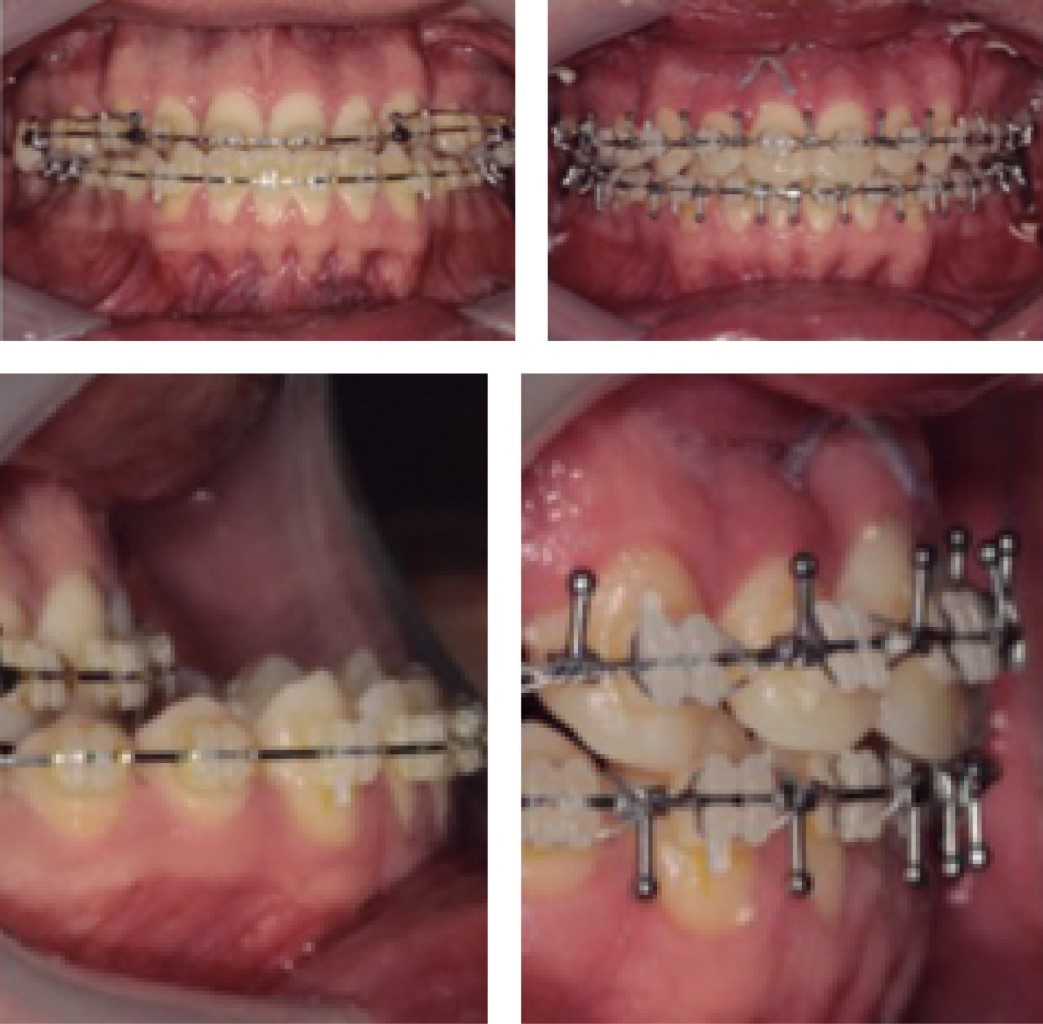

En la cavidad oral se identifica un maxilar sobreexpandido dentoalveolarmente, extracción de primeros premolares superiores y desviación de la línea media superior 2.5 mm hacia la derecha. Maloclusión molar y canina clase III de Angle. Mordida cruzada anterior y overjet negativo de 21 mm (Figura 3).

En la actualidad, el paciente se encuentra en tratamiento ortodóncico postoperatorio en fase de cierre de espacios para después continuar con la fase de asentamiento y detallado (Figuras 7, 8, 9, 10, 11, 12, 13 y 14).

Figura 3

Figura 7

Figura 8